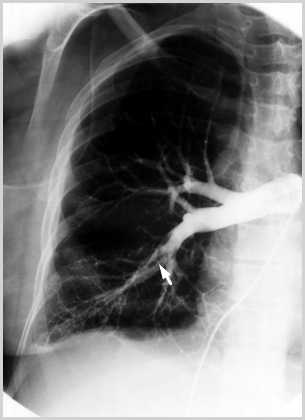

Figure 7: Pulmonary angiogram

This angiogram is similar to our patient's. It demonstrates filling defects in the right lower lobe and shows no perfusion to the right middle lobe.